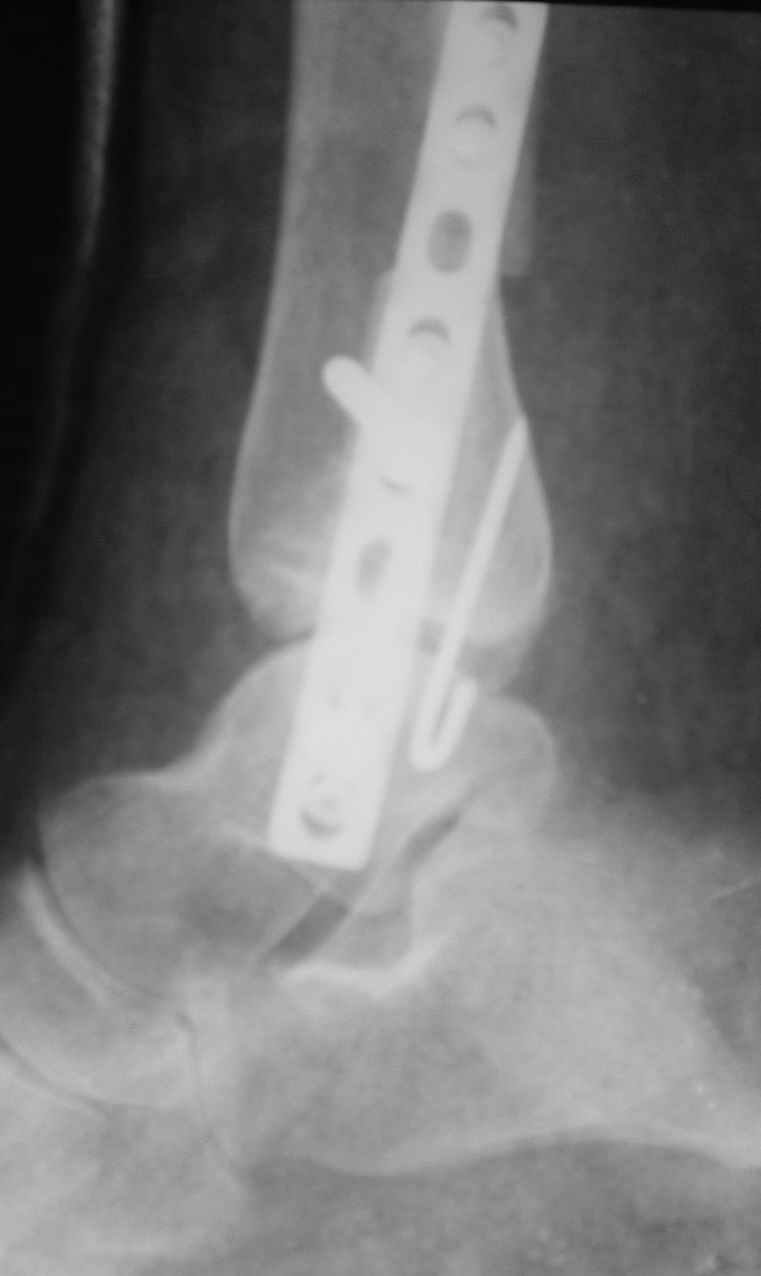

Уважаемые коллеги! Персонально, дорогой доктор Джолдас. Не знаю, почему почта к тебе не проходит - у меня почтовая программа "Bat", снимки в JPG. Выставляю через форум. 10 апреля я показывал снимки больной с застарелым переломо-вывихом голеностопного сустава. 9 июня прооперировал, снимки прилагаю. R-контроль через месяц ходьбы на костылях, все стоит также. Разрешил частичную (20кг) нагрузку на ногу, пока жалоб нет.

Ход операции - сагиттальная остеотомия по линии неправильно сросшегося перелома малоберцовой кости, остеотомия с формированием внутренней лодыжки, попытка вправления подвывиха неудачна из-за того, что "не хватало" длины малоберцовой. Остеотомия малоберцовой кости выше синдесмоза. Остеосинтез.